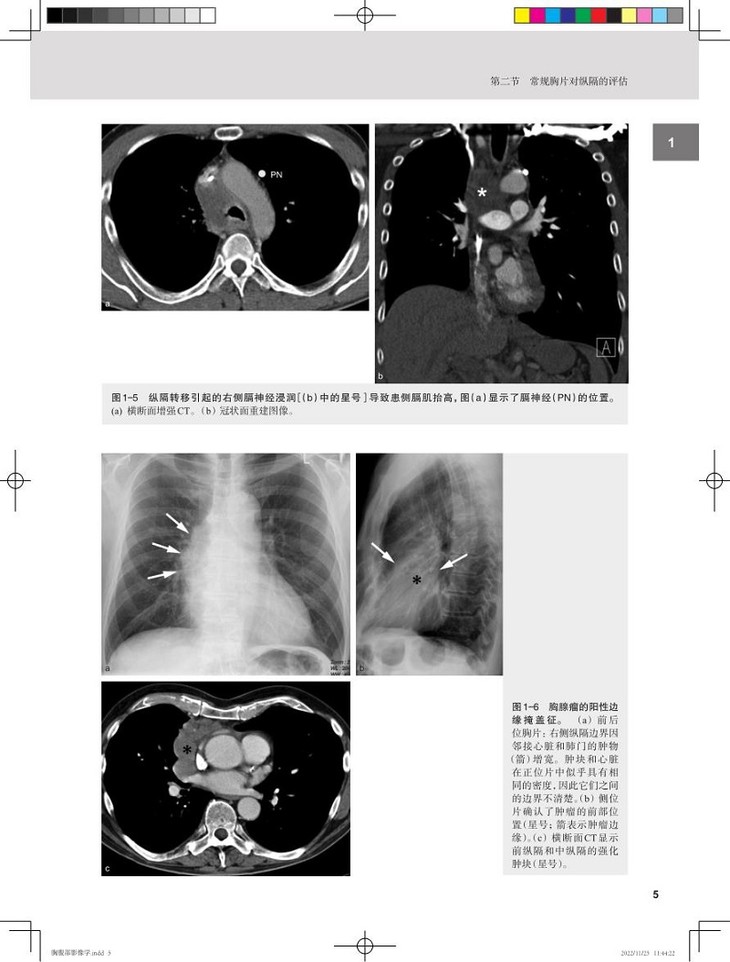

本书是一部精练的胸腹部影像医学精要,内容分为两大部分,第一部分胸部,包括纵隔、心脏和心包、大血管、肺和胸膜4 章;第二部分腹部,包括肝脏、胆囊和胆道、胰腺、消化道、脾和淋巴系统、肾上腺、肾脏和尿道、女性盆腔、男性盆腔9章,每种疾病都从定义、影像征象、临床特征、鉴别诊断和关键点等角度进行阐述,特别强调临床表现、解剖标志与影像表现结合的读图方法,指出每种疾病首shou选检查方法及各种检查方法优缺点,并对重点内容进行了提炼,以“提醒”“警惕”单独列出。